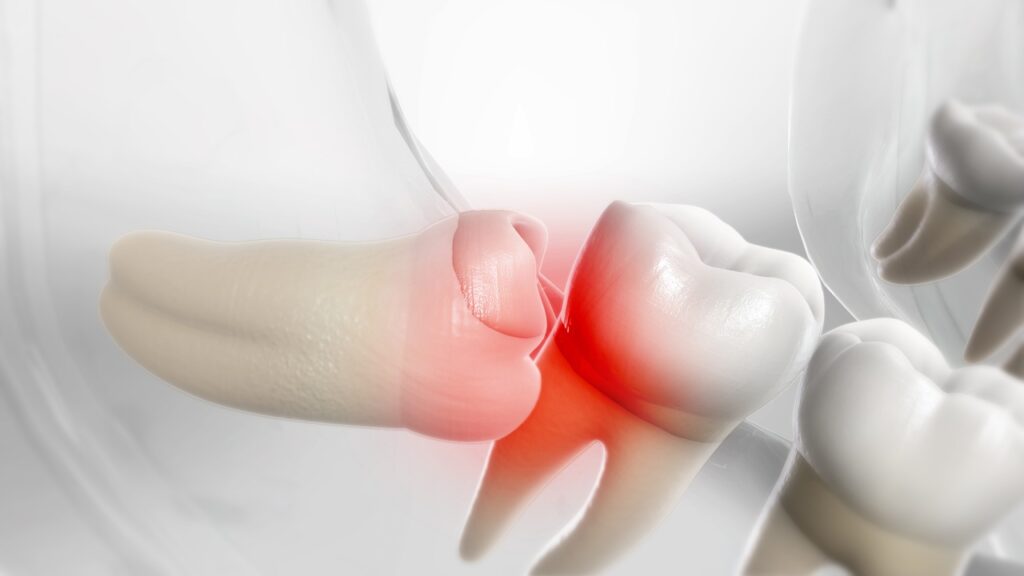

Ảnh hưởng đến xương và hàm răng

Răng khôn mọc lệch đâm vào răng lân cận có thể gây hủy hoại chiếc răng đó và làm lung lay tiêu xương, lúc này buộc phải nhổ răng ngay. Dấu hiệu thường xuất hiện của triệu chứng này là đau âm ỉ kéo dài ở vị trí đó. Nếu không được chữa trị kịp thời, nhiễm trùng có thể lan đến các khu vực như tai, má, mắt, cổ… và gây nguy hiểm đến tính mạng.